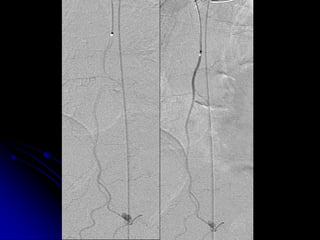

• FLUOROSCOPY

• IMAGING GUIDED RX/DX